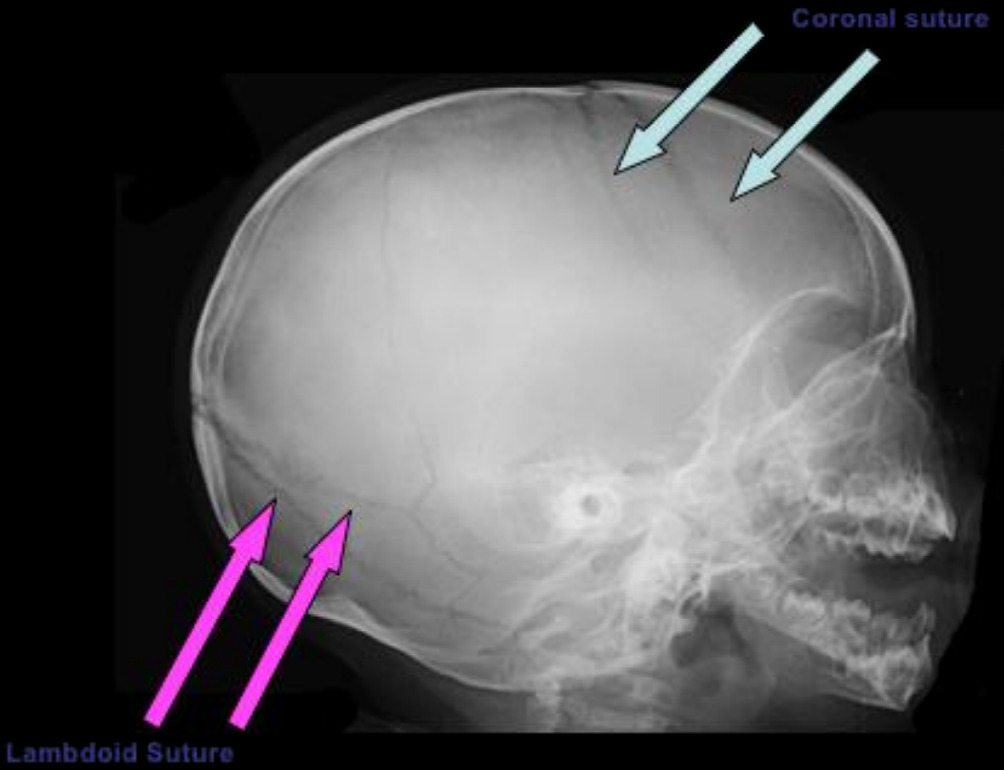

¿Qué diferencia una sutura de una fractura en RX?

• Sutura: borde serrado, línea curva, + clara, 📍 anatómica fija

• Fx: borde liso, línea recta, + oscura, atraviesa suturas